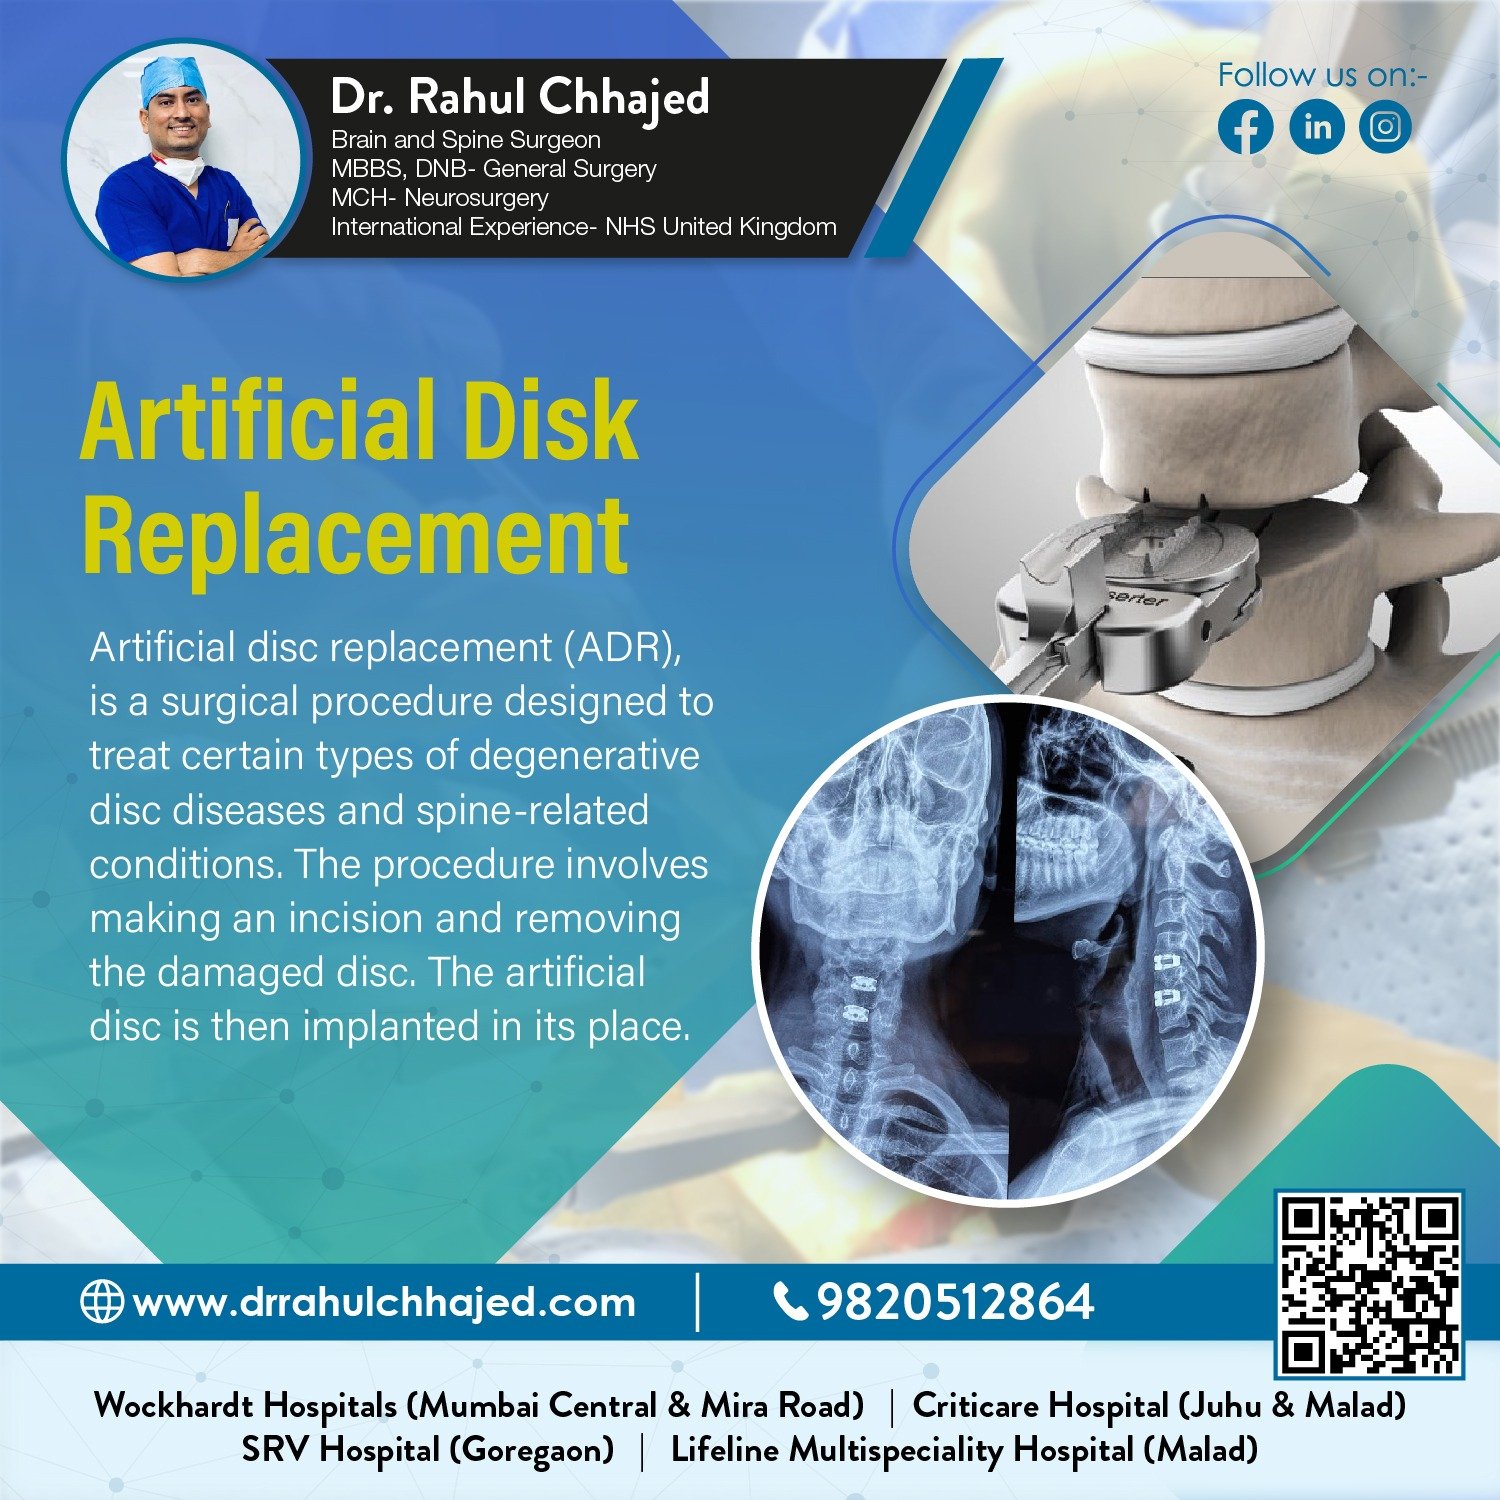

Spine Surgery

Dr. Rahul is a highly experienced spine surgeon specializing in diagnosing and treating spinal conditions. He performs a wide range of surgical options for spinal conditions, including minimally invasive techniques, spinal fusion, and disc replacement.